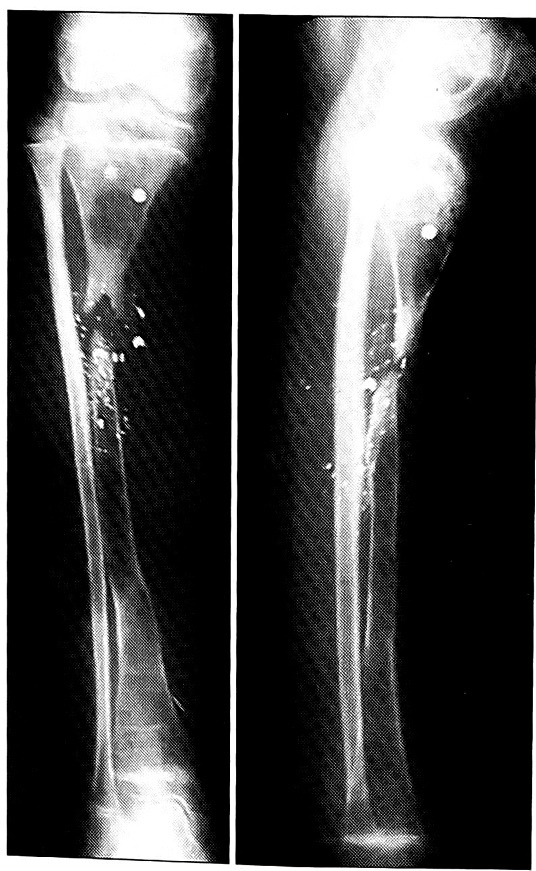

Рис. 1. Больная М. Рентгенограммы голени до начала лечения.

Больная М.,12 лет, поступила с рубцовым дефектом кожных покровов, дефектом большеберцовой кости, застарелым повреждением малоберцового нерва, вторичной нейрогенной эквинусной деформацией стопы вследствие огнестрельного ранения правой голени (рис. 1).

Первым этапом имплантированы два эндоэкспандера на боковые поверхности голени с целью создания прироста кожи и последующей кожной пластики местными тканями (рис. 2). После восстановления полноценных кожных покровов произведена двухэтапная костная пластика дефекта большеберцовой кости: первый этап — закрытое наложение аппарата Илизарова для выявления истинного размера дефекта большеберцовой кости, второй этап — пластика дефекта костным аутотрансплантатом, взятым с противоположной голени (рис. 3).